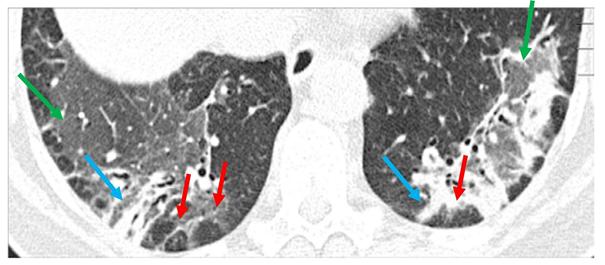

Medicatie-geïnduceerde longziekten zijn een steeds vaker voorkomende bijwerking van diverse geneesmiddelen. Ze worden vooral gezien bij gebruik van (nieuwere) oncologische middelen zoals immuuntherapie, maar ook van bijvoorbeeld klassieke chemotherapeutica, immunosuppressiva bij auto-immuunziekten, amiodaron bij hartritmestoornissen of nitrofurantoïne bij urineweginfecties. De radiologische presentatie varieert van diffuus matglas (niet-specifieke interstitiële pneumonie), consolidaties (organiserende pneumonie) tot fibrose of zeldzamere patronen zoals hypersensitiviteitspneumonitis. Het stellen van de klinische diagnose is uitdagend door aspecifieke symptomen en vereist uitsluiting van infectie, hartfalen en andere oorzaken. Beeldvorming is hierbij een essentieel instrument. De behandeling bestaat uit het (meestal tijdelijk) staken van de verdachte medicatie en eventueel corticosteroïden, te bepalen in multidisciplinaire besluitvorming. De ernst van het longbeeld bepaalt de prognose, die varieert van volledig herstel tot een hoge mortaliteit bij diffuse alveolaire schade. Alertheid bij nieuwe longafwijkingen is cruciaal, waarbij de radioloog een belangrijke signalerende rol heeft.